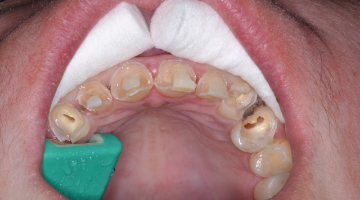

I knew Sarah when she was well and could smile at the world. Then, when the painful loss of a loved one dismantled her life, having no safety net or support, depression set in. Later, substance abuse took over, and eventually Sarah hit rock bottom. Thankfully, a local family took her in, and she is reclaiming her life. But her teeth and smile were devastated (figures 1 and 2).

Traditional treatment options would be full-mouth reconstruction (FMR) or full-mouth extractions and dentures. There were only a few teeth in her mouth that did not have advanced decay, so FMR would necessitate root canals, build-ups, and porcelain restorations. With limited finances and a history of neglect, most practitioners might be inclined to write off the patient and prepare her for dentures, and the thought entered my mind as well. Having known Sarah during happier times, however, I wanted something better for her. But what type of restorative treatment should I attempt?